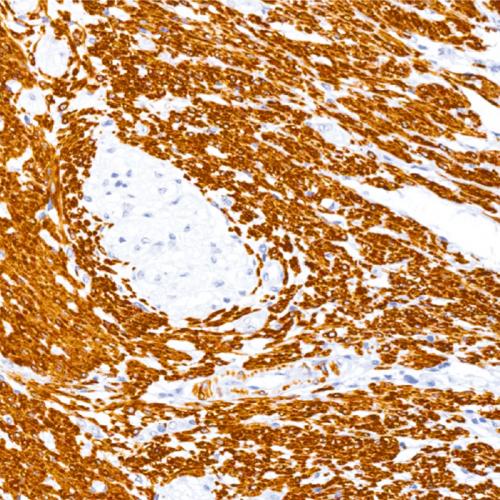

我國(guó)胃癌發(fā)病率居惡性腫瘤第2位,新發(fā)病例68萬(wàn)例,死亡49萬(wàn)例。研究表明:HP感染者均會(huì)引起慢性活動(dòng)性胃炎,在胃黏膜萎縮和腸化生的發(fā)生和發(fā)展中也起重要作用[1],HP感染和胃癌的發(fā)生密切相關(guān),根除HP是預(yù)防胃癌的有效措施。IHC染色特異性強(qiáng)、靈敏度高、陽(yáng)性準(zhǔn)確性高、易于判讀,便于各級(jí)醫(yī)院病理科開(kāi)展業(yè)務(wù),特別適合胃鏡活檢標(biāo)本量較大的情況,值得推廣[2-3]。